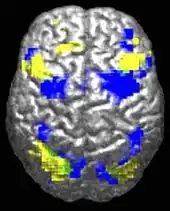

A human brain viewed from above. About 10% is highlighted in yellow and 10% in blue. There is a tiny green region (~0.5%) where they overlap.

Autistic individuals tend to use different brain areas (yellow) for a movement task compared to a control group (blue).[26]

The underconnectivity theory of autism posits that autistic people tend to have fewer high-level neural connections and less global synchronization, along with an excess of low-level processes.[27] Functional connectivity studies have found both hypo- and hyperconnectivity in brains of autistic people.[28] Hypoconnectivity is commonly observed for interhemispheric and cortico-cortical functional connectivity.[29] Some studies have found local overconnectivity in the cerebral cortex and weak functional connections between the frontal lobe and the rest of the cortex.[30] Abnormal default mode network (task-negative) connectivity is often observed. Toggling between task-negative network activation and task-positive network activation (consisting of the dorsal attention network and salience network) may be less efficient, possibly reflecting a disturbance of self-referential thought.[31] Such patterns of low function and aberrant activation in the brain may depend on whether the brain is performing social or nonsocial tasks.[32]